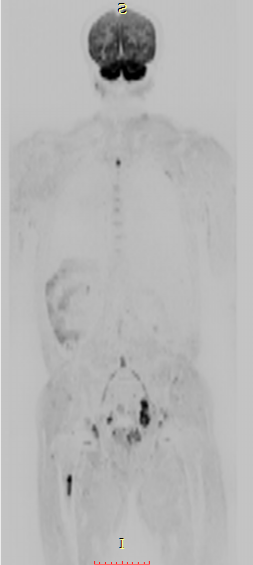

七、全身类PET成像,此项检查技术主要用于全身转移肿瘤的筛查:

①磁共振类 PET成像对全身恶性肿瘤病变性质的诊断,尤其对全身转移灶的筛查,淋巴结转移筛查及恶性肿瘤的分期评估具有很高的价值。②对已明确发现转移性病灶寻找其原发灶;术后放化疗的效应观察等具有较大优势。③对高危人群的肿瘤筛查具有实用价值。

联影磁共振怎么样平原县第一人民医院联影uMR780 光梭3.0T磁共振正式投入使用,开启医学影像新时代!_https://www.jmylbn.com_新闻资讯_第17张

联影磁共振怎么样平原县第一人民医院联影uMR780 光梭3.0T磁共振正式投入使用,开启医学影像新时代!_https://www.jmylbn.com_新闻资讯_第18张

联影磁共振怎么样平原县第一人民医院联影uMR780 光梭3.0T磁共振正式投入使用,开启医学影像新时代!_https://www.jmylbn.com_新闻资讯_第19张

联影磁共振怎么样平原县第一人民医院联影uMR780 光梭3.0T磁共振正式投入使用,开启医学影像新时代!_https://www.jmylbn.com_新闻资讯_第20张

联影磁共振怎么样平原县第一人民医院联影uMR780 光梭3.0T磁共振正式投入使用,开启医学影像新时代!_https://www.jmylbn.com_新闻资讯_第21张

联影磁共振怎么样平原县第一人民医院联影uMR780 光梭3.0T磁共振正式投入使用,开启医学影像新时代!_https://www.jmylbn.com_新闻资讯_第22张

联影磁共振怎么样平原县第一人民医院联影uMR780 光梭3.0T磁共振正式投入使用,开启医学影像新时代!_https://www.jmylbn.com_新闻资讯_第23张